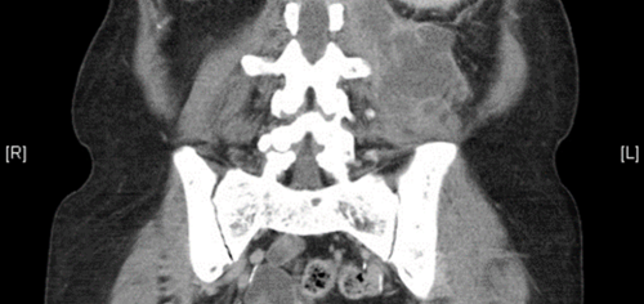

Uroradiology